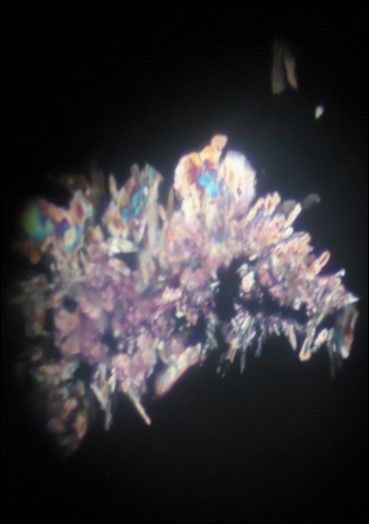

Figure 5.Calcium oxalate crystals showing birefringence under polarized light.